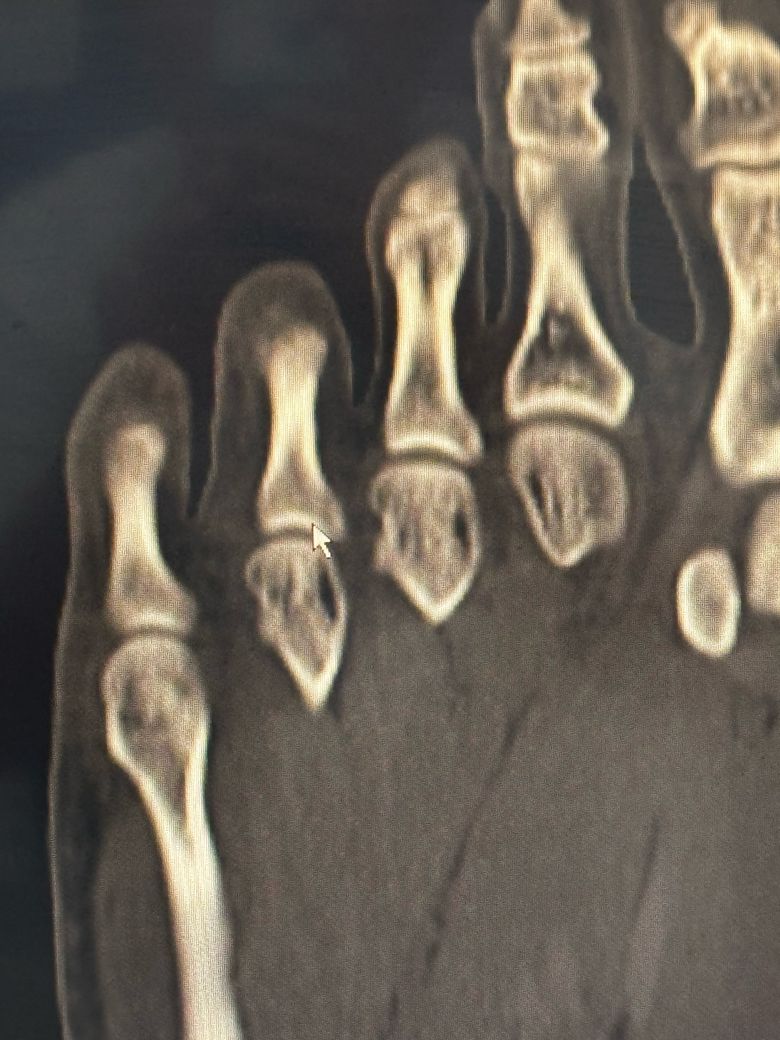

• 1번 째 사진

이미지상 발가라 뼈에 금이 가거나 골절 소견이 있어보이지만 정확한 수술 여부는 골절의 위치 각도 뼈 어긋남 여부에 따라 다릅니다.

발가락 골절로 인한 수술 관련해서 질문을 주셨는데 골절의 정도 및 어긋남 정도 그리고 증상에 따라 수술 여부가 결정될 수 있으며 발가락이 휘어져 보이거나 뼈가 많이 어긋나거나 관절에 영향을 주는 골절 같은 경우 수술이 필요할 수 있습니다.